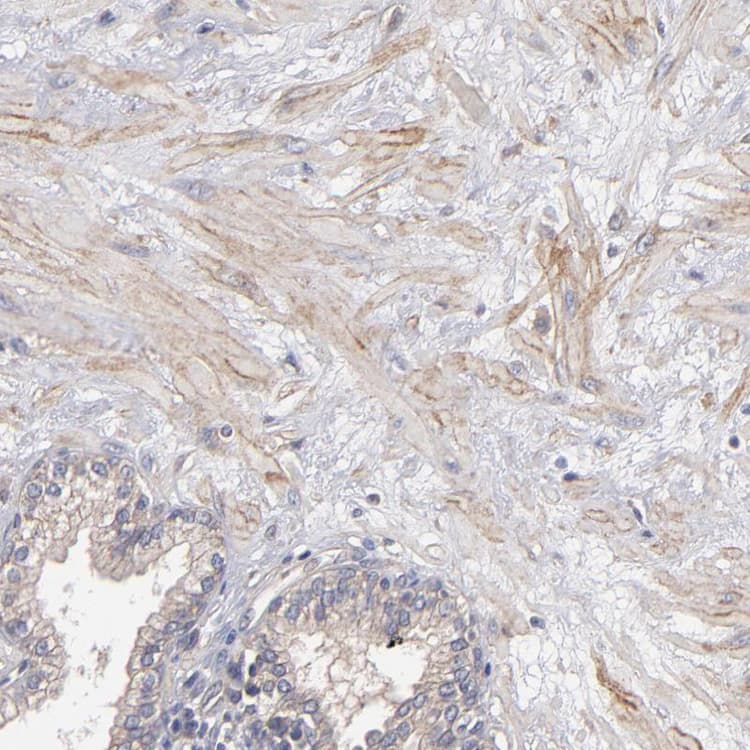

Rabbit Polyclonal Dystrophin antibody. Suitable for IHC-P and reacts with Human samples. Immunogen corresponding to Recombinant Fragment Protein within Human DMD aa 150-350.

Applications IHC-P

Species Reactivity Human